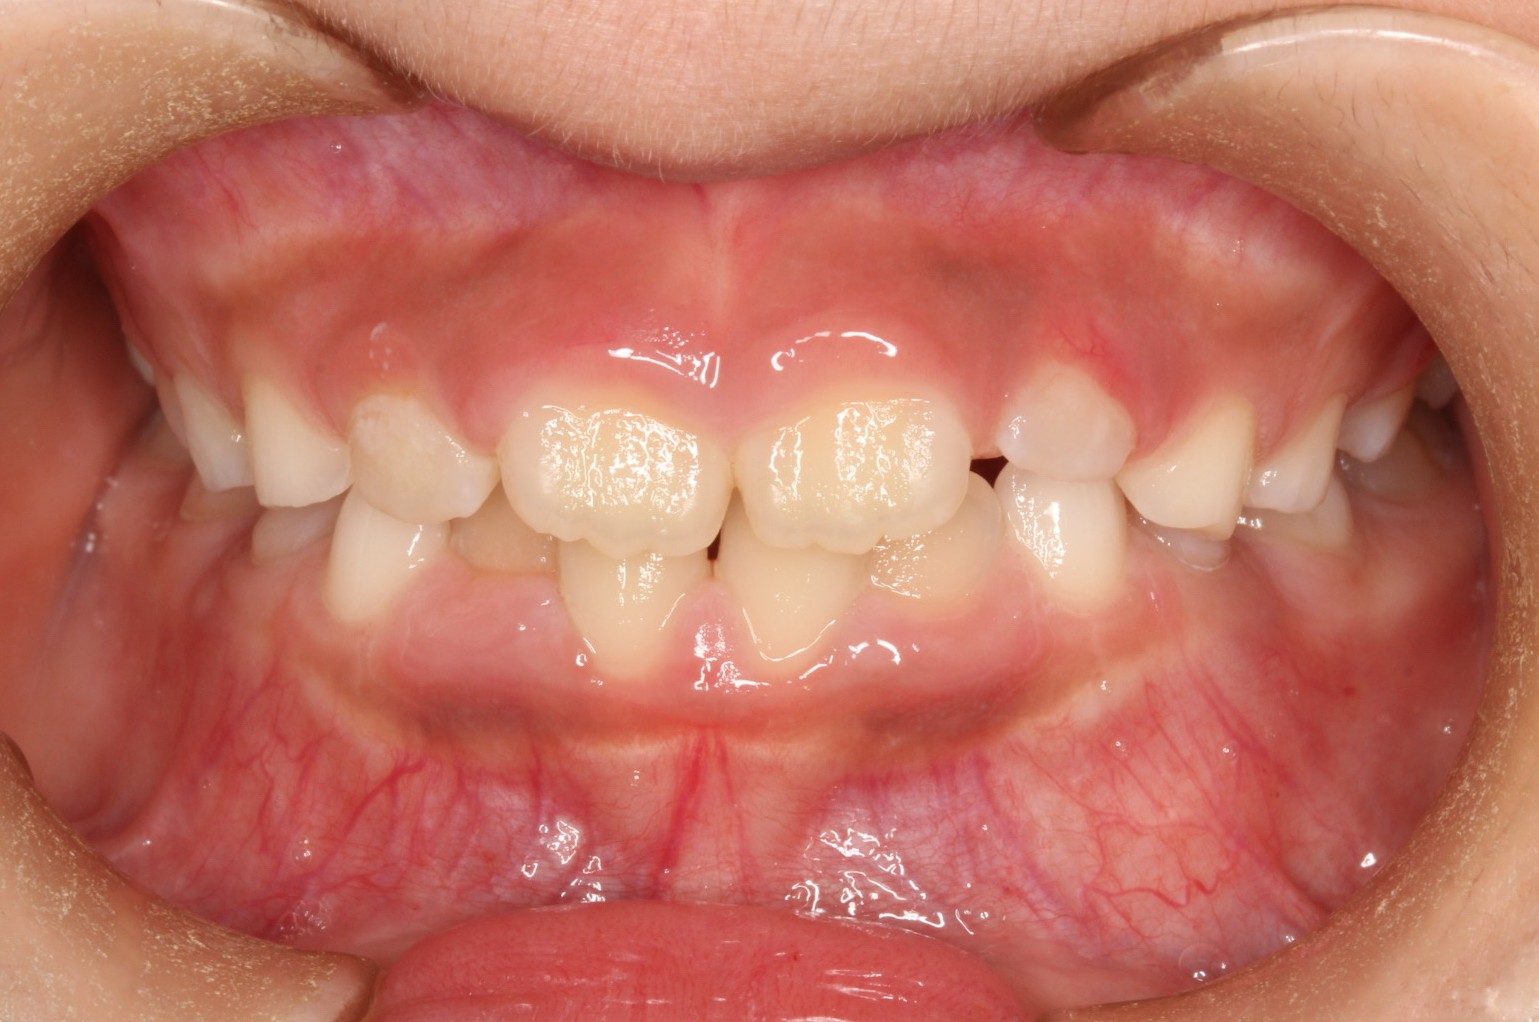

矯正術前:正面

今回ご紹介する患者様は、上下の叢生を気にされており、矯正検査後叢生Ⅰ級(Ⅲ級傾向)と診断いたしました。

| 主訴 | 上下の叢生が気になる |

| 治療内容 | 患者様は上下の叢生を気にされており、矯正検査後叢生Ⅰ級(Ⅲ級傾向)と診断いたしました。 |